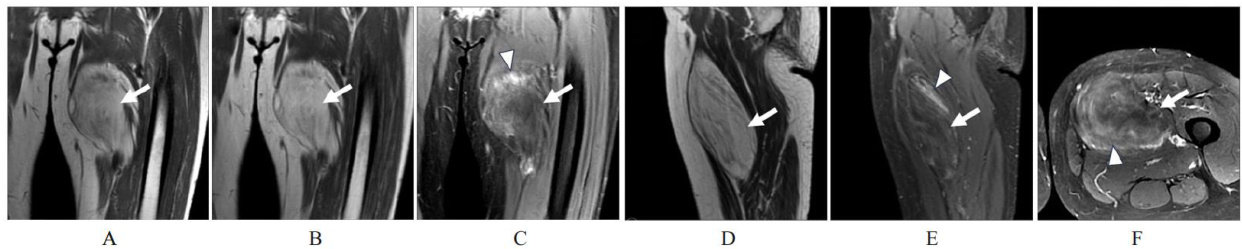

ABSTRACT Atypical lipomatous tumor (ALT) is a rare soft tissue sarcoma originating from adipocytic tissue.The clinical manif(剩余11324字)

左下肢非典型脂肪瘤样肿瘤1例报告及文献复习